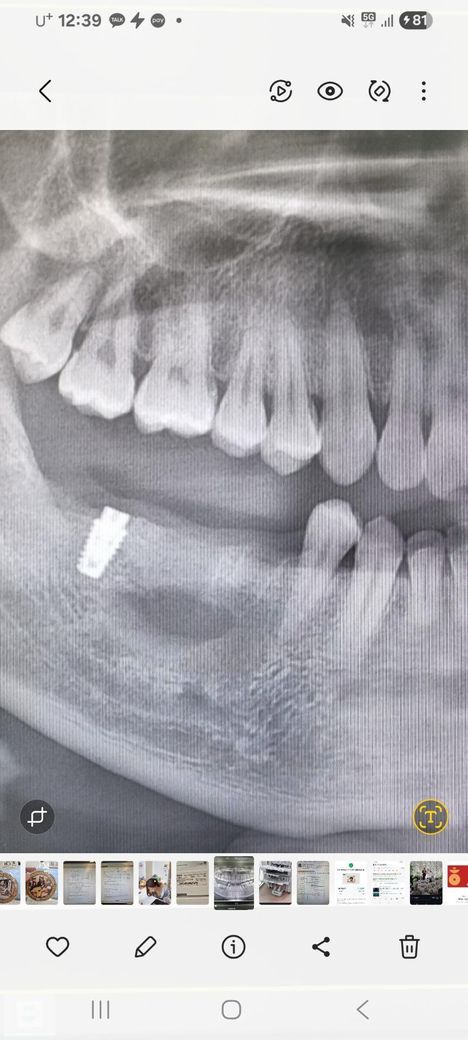

그렇게 수술 후 약 50여일정도 지난 시점으로 최근 xray(2번째 사진) 찍으니 뼈가 많이 복원되었다고 하면서, 송곳니 옆 작은 어금니 자리와 올초에 박은 임플란트 나사쪽 2개에 임플란트 시술을 하자고 합니다. (구멍이 큰 나머지 한곳은 내년에 시술)

• 2번 째 사진

적절한 조치로 뼈 상태가 많이 회복되긴 했네요. 근데 엑스레이상은 2차원 단면적인 거고, 수술 할 때 필드를 열어봐야 뼈 상태를 명확히 알 수 있습니다. 주치의가 판단해서 잇몸 절개해서 열어보고 심을만하면 심을거고, 아니면 덮고 나올겁니다.